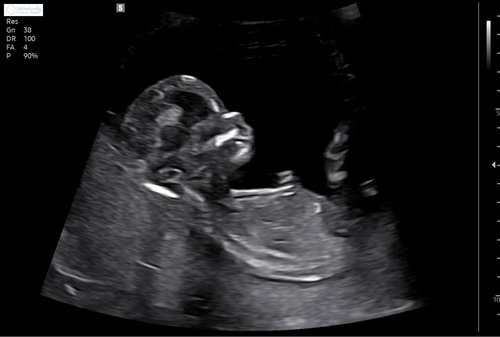

Deze

Dit zijn de foto's die ik heb, ik ben benieuwd heb er zelf totaal geen verstand van 馃グ

Hier staat hij net niet op helaas